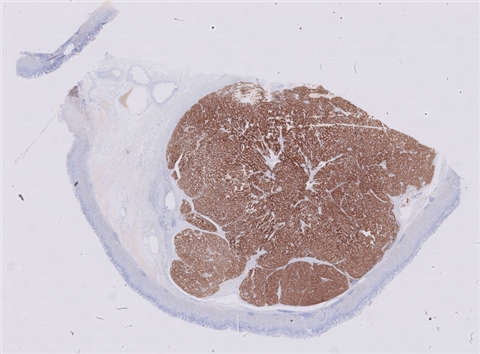

案例4 (6960)

性别:       年龄:10

患者详情: 主诉:视物模糊1月余,发现抽搐、双下肢活动障碍、声音嘶哑10余天。 10-6 CT示腹膜后不规则软组织占位; 10-16彩超示腹主动脉周边前侧肾动脉平面可见一大小约为44*48*25mm的低回声团块,临近腹主动脉,边界尚清晰,形态欠规则,内部回声不均匀,未及明显钙化及液性暗区。

大体所见: 结节状组织一个: 4. 2cm*3cm*2.3cm,切面灰红灰黄。

免疫组化: NSE(3+)、Syn(3+)、CgA(3+)、CD99胞质(+)、WT-1(+)、INI-1(+)、CK广谱(-)、CD10(-)、TFE3(-)、Inhibina(-)、HMB45(+)、CD56(3+)、TLE1(-)、S-100(+)、Pax-8(+)、calretin(-)、Alk(-)、Fil-1(-)、CyclinD1(-)

医院: 江西省儿童医院